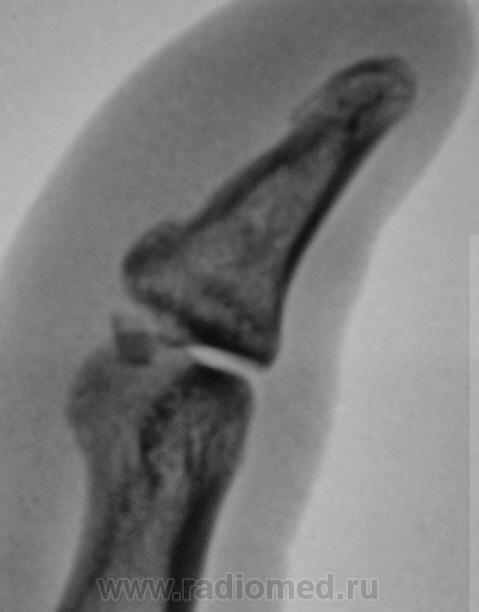

Пол пациента: Мужской пол Тип патологии: Травма Область исследования: Скелетно-мышечная система Методы исследования: Rg Что это? Отколовшийся фрагмент или чсто-то другое? Травма была накануне. Обратился к хирургу поликлиники, направлен хирургом на рентгенографию. https://radiomed.ru/sites/default/files/styles/case_slider_image/public/user/12/2.P5200014.JPG?itok=kSaxtyoS https://radiomed.ru/sites/default/files/styles/case_slider_image/public/user/12/3.P5200014a.jpg?itok=XP5p8ESI https://radiomed.ru/sites/default/files/styles/case_slider_image/public/user/12/4.P5200014v.jpg?itok=CE-t0-Id https://radiomed.ru/sites/default/files/styles/case_slider_image/public/user/12/5.P5200014vu.jpg?itok=D6GOyUSZ ID:3946 Thu, 20/05/2010 - 20:38 #1 Ola-la Offline Last seen: 10 months 3 weeks ago Joined: 06.12.2008 - 09:33 Posts: 1786 Это перелом. https://www.instagram.com/pediatricradiology/ Thu, 20/05/2010 - 20:49 #2 Анатолий Владим... Offline Last seen: 7 years 10 months ago Joined: 16.10.2009 - 21:16 Posts: 1941 Есть перелом... Thu, 20/05/2010 - 23:14 #3 Илья Васильевич... Offline Last seen: 13 years 11 months ago Joined: 25.04.2010 - 14:23 Posts: 89 перелом. телу- мера, душе-Вера

Это перелом.

Есть перелом...